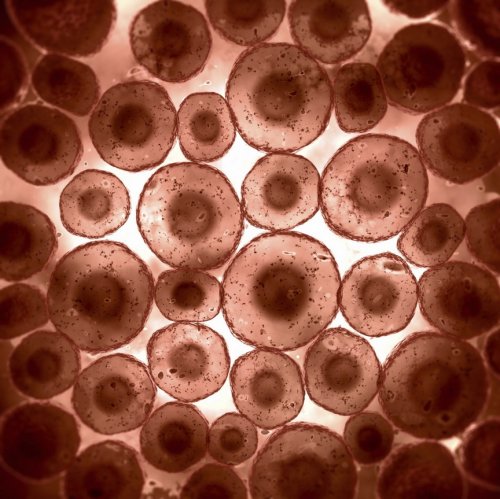

14. Наши клетки никогда не перестают воспроизводиться

Клетки являются строительными блоками организма. Каждую секунду человеческое тело производит 25 миллионов новых клеток. Для сравнения, за каждые 13 секунд клеток вырабатывается больше, чем численность населения США.

11. Большинство наших клеток не являются человеческими

Из миллиардов клеток, составляющих человеческое тело, лишь около 10 процентов на самом деле «человеческие». Остальные 90 процентов состоят из различных грибков и бактерий.